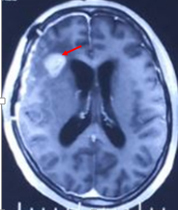

另一例患者到某医院行手术治疗。肿瘤部分切除后,诊断胶质瘤II级,术后常规给予放疗及化疗。术后为期6周的放化疗还没有结束,复查磁共振又发现额部有结节状病灶。

红色箭头标注处是治疗进行中出现的“阴影”、“结节”

经过多个专业的专家会诊后,结合DWI,灌注,波谱等,前面病例考虑为急性局灶性梗死可能性大,后者考虑治疗后改变可能。当然,虽然患者听到这些话长舒一口气,医生们还是更为谨慎,定期复查或者更频密复发,必要时行PET-CT检查都是有必要的。